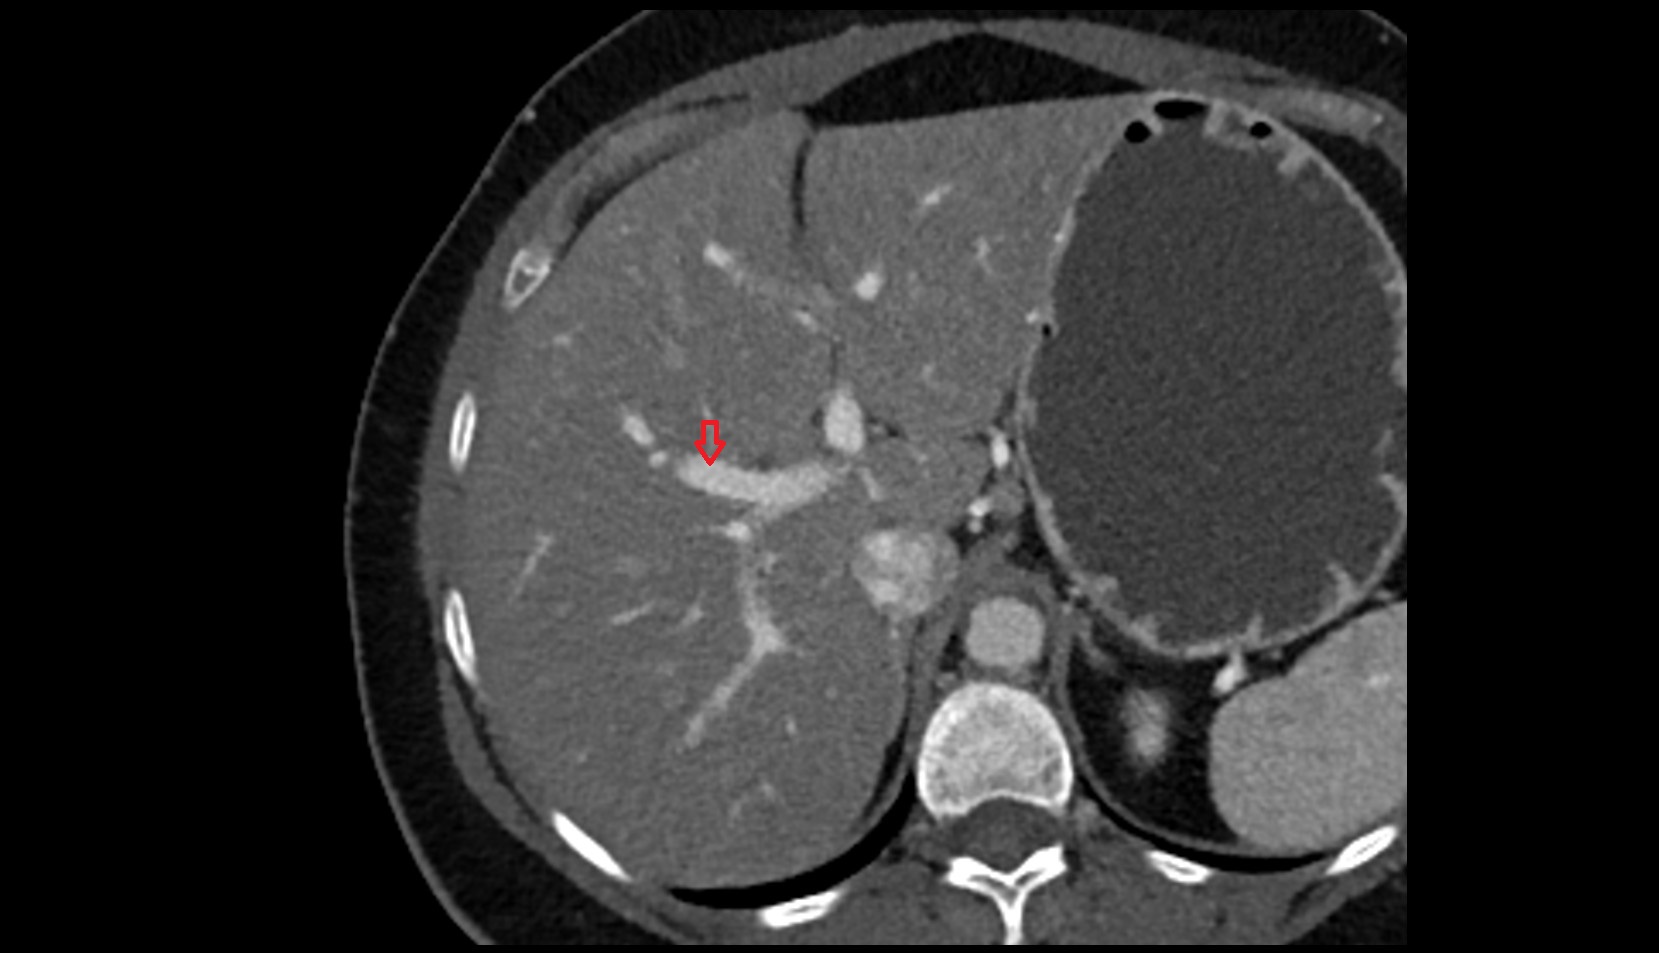

- Right lobe of liver

- Liver

- Liver Segment V – Right anteroinferior segment

- Liver Segment VI – Right posteroinferior segment

- Liver Segment VII – Right posterosuperior segment

- Liver Segment VIII – Right anterosuperior segment